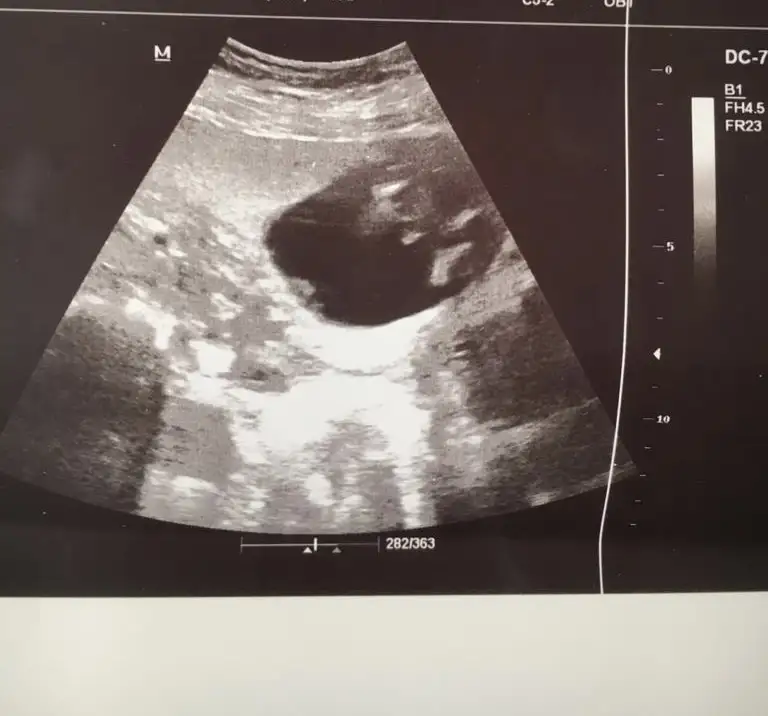

Ikra meyra Ikra meyra canim gecen sene kizimi tahminde dogru bilmistin 13+3haftalik tekrar gebeyim bi tahminde bulunurmusun bugun gittim devlette 16.haftaya kadar yasal olmadigi icin demiyorlarya dr al sen bak dedi verdi güldu🙃

Yaaa maşallah 🧿 kız gibi sanki emin olamadım